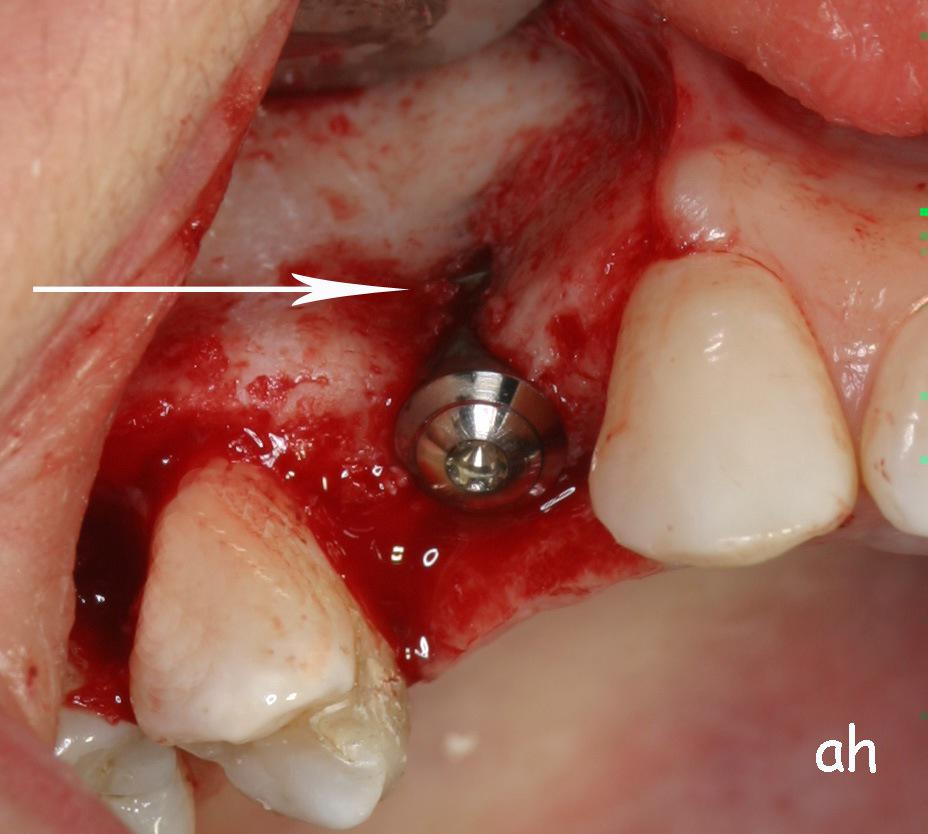

Exemple 11: Pendant l'implantation on remarque un manque d'os sur la partie externe, les spires de l'implant sont visibles.

Exemple 11: Une greffe d'os est effectuée afin de compenser l'épaisseur d'os manquante.

Exemple 11: Le tout est recouvert d'une membrane collagène.